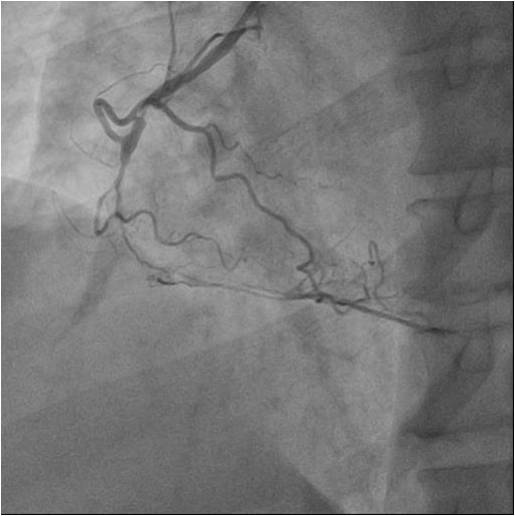

Relevant Catheterization Findings

Numerousattempts of antegraderecanalization using guidewires of different stiffnesswere unsuccessful. Pts ofretrograde recanalization using guidewires of different stiffnesswereunsuccessful. Another attempt at antegraderecanalization led to dissection dista RCA. Retrograde recanalization was performed using the technique of «kissing-wire». retrograde guidewire was inserted into theproximal segment of the RCA. Guidewire was externalized into the guide catheterusing Reverse CART technique. The tip-in technique was used for the Corsairantegrade microcatheter over the retrograde wire. Tthe microcatheterwassuccessfully inserted into the distal segment of the RCA. A soft antegradeguidewire was placed. A balloon catheter 2.0x30 mm was used for predilation inthe proximal middle and distal segments of the RCA at 14 atm. Consecutive DES2.75x44mm, DES 2.75x44mm, DES 3.5x39 mm stents were implanted in the distal,middle and proximal segments of the RCA, at pressures up to 16 atm.